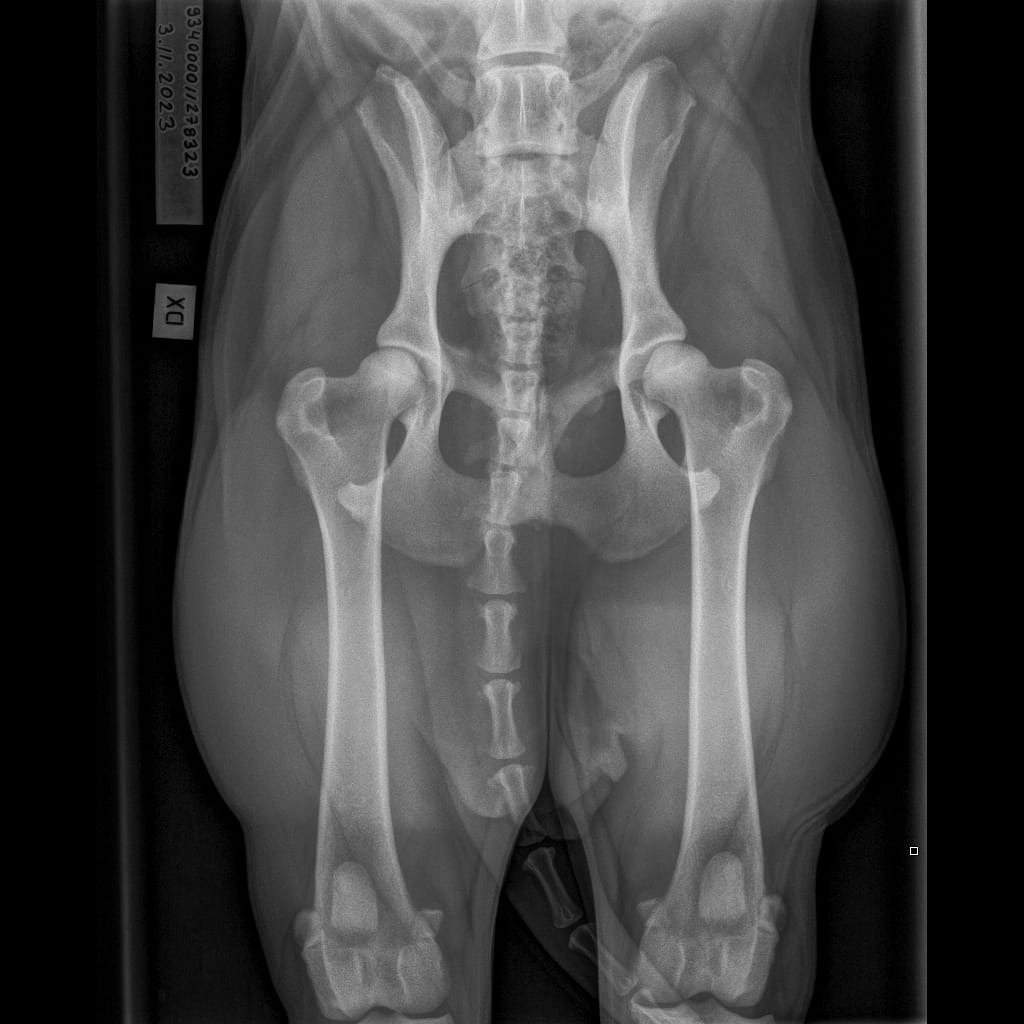

| Name | ID | Birth weigth | Ridge | Height | Weight | Bite | Hips | Elbows | Shoulders | Spine | MH | Other |

|---|---|---|---|---|---|---|---|---|---|---|---|---|

| Lumottu Uljas Iivonpoika ft. Finnridge | Blue ♂︎ | 505 g | Correct | TBA | TBA | TBA | B/B | 0/0 | Unaffected/Unaffected | LTV1, SP0, VA1 | MH, gunshot proof | Low-grade MCT removed 06/2024 |

| Lumottu Aatos Iivonpoika ft. Finnridge | Turqoise ♂︎ | 530 g | Correct | TBA | TBA | TBA | B/B | 0/0 | Unaffected/Unaffected | LTV2, SP0, VA0 | MH, gunshot proof | |

| Lumottu Martta Iivontytär ft. Finnridge | Lime ♀︎ | 525 g | Correct | TBA | TBA | TBA | A/A | Xray: 0/0 CT: 3/1 | Unaffected/Open to interpretation | LTV0, SP0, VA0 | MH, unfamiliar to gunshot | |

| Lumottu Armas Iivonpoika ft. Finnridge | Orange ♂︎ | 440 g | Correct | TBA | TBA | TBA | A/A | 0/0 | Unaffected/Unaffected | LTV0, SP0, VA0 | MH, unfamiliar to gunshot | |

| Lumottu Aulis Iivonpoika ft. Finnridge | Aqua ♂︎ | 440 g | Correct | TBA | TBA | TBA | B/B | 1/1 | Unaffected/Unaffected | LTV1, SP0, VA0 | Handler interrupted | |

| Lumottu Irma Iivontytär ft. Finnridge | Pink ♀︎ | 550 g | Correct | TBA | TBA | TBA | C/B (low sockets) | 0/0 | Unaffected/Unaffected | LTV0, SP0, VA0 | Spring 2024 | |

| Lumottu Sirkka Iivontytär ft. Finnridge | No collar ♀︎ | 390 g | Ridgeless | TBA | TBA | TBA | A/A | 0/0 | Unaffected/Unaffected | LTV1, SP0, VA0 |